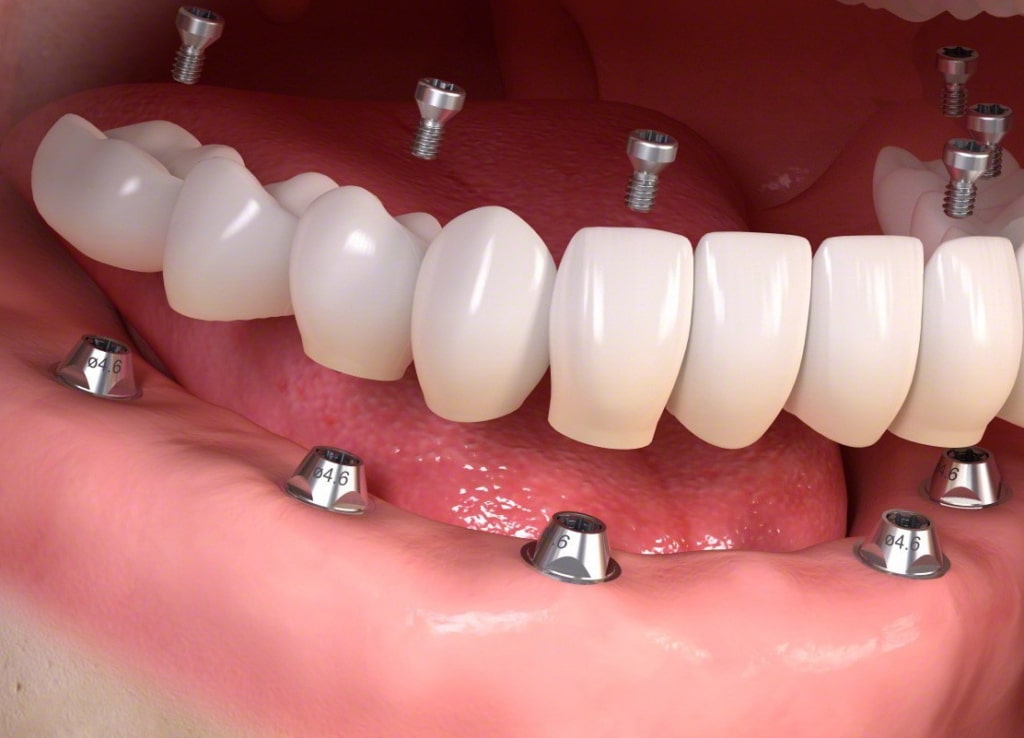

Implantologia moderna computer assistita

(senza incisioni e punti di sutura)

L'approccio dell'implantologia guidata offre numerosi vantaggi ai pazienti perché guidata, appunto, da tecnologie digitali, nello specifico computer, scanner e radiografie digitali 3D.

L'intervento chirurgico in questo caso non solo garantisce una maggiore prevedibilità dei risultati, ma anche una maggiore precisione e una minore invasività.

L'implantologia guidata permette di eseguire un intervento senza incidere le gengive e senza punti di sutura perché pianifichiamo al computer la posizione esatta degli impianti sulla base della Tac Cone Beam eseguita. Successivamente attraverso una mascherina di posizionamento inseriremo in modo facile e veloce gli impianti senza eseguire alcun apertura di gengiva. Non incidere le gengive significa guarigione rapida e riduzione al minimo dei dolori e gonfiori post operatori.